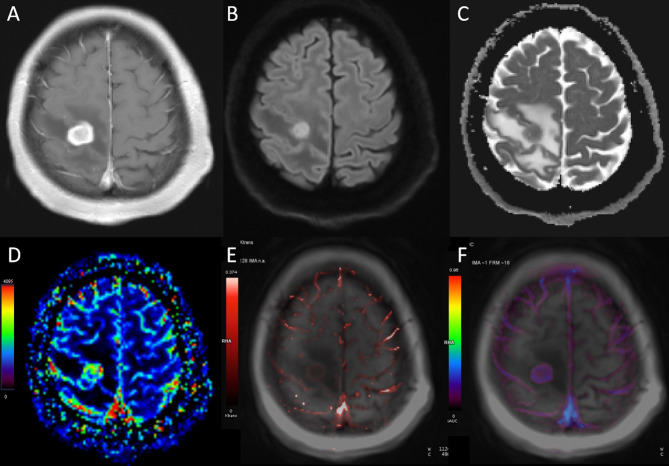

Purpose: The differential diagnosis of primary central nervous system lymphoma (PCNSL) and atypical glioblastoma (aGBM) exhibiting homogeneous enhancement and negligible necrosis poses a significant challenge for conventional MRI. The study aims to investigate diffusion-weighted imaging (DWI), dynamic contrast-enhanced (DCE) MRI, and contrast agent (CA) preload dynamic susceptibility contrast perfusion-weighted imaging (DSC-PWI) to differentiate aGBM and PCNSL.

Materials and methods: This retrospective study analyzed 27 patients with aGBM (solid enhancement without visible necrosis) and 105 patients with PCNSL, all undergoing preoperative DWI, DCE-MRI, and CA preload DSC-PWI. The relative apparent diffusion coefficient (rADC) and relative cerebral blood volume (rCBV) were obtained from DWI and DSC-PWI. The pharmacokinetic parameters (Ktrans, Ve, Kep, and iAUC) were acquired using DCE-MRI. The independent-samples t-test and Mann-Whitney U test were utilized to compare parameters. A binary logistic regression analysis was performed to assess the combined effect of various parameters. Before regression analysis, collinearity analysis of parameters was performed. The diagnostic capability of each parameter and their combination were evaluated by receiver operating characteristic (ROC) with area under the curve (AUC) and compared with DeLong test.

Results: In comparison to aGBM, the Ktrans, Ve, and iAUC were significantly elevated in PCNSL, whereas the rCBV and rADC were significantly lower (p < 0.05 for all comparisons). Meanwhile, these parameters allowed excellent diagnostic performance (AUC = 0.817 [rCBV], 0.751 [rADC], 0.808 [Ktrans], 0.765 [Ve], and 0.801 [iAUC]; DeLong test, p > 0.05 for all comparisons). Notably, the combination of all these parameters significantly increased the probability of distinguishing aGBM from PCNSL (AUC = 0.966).

Conclusions: DWI, DCE-MRI, and CA preload DSC-PWI can effectively differentiate aGBM from PCNSL, and the combination of all three techniques significantly enhances the discriminatory efficacy.